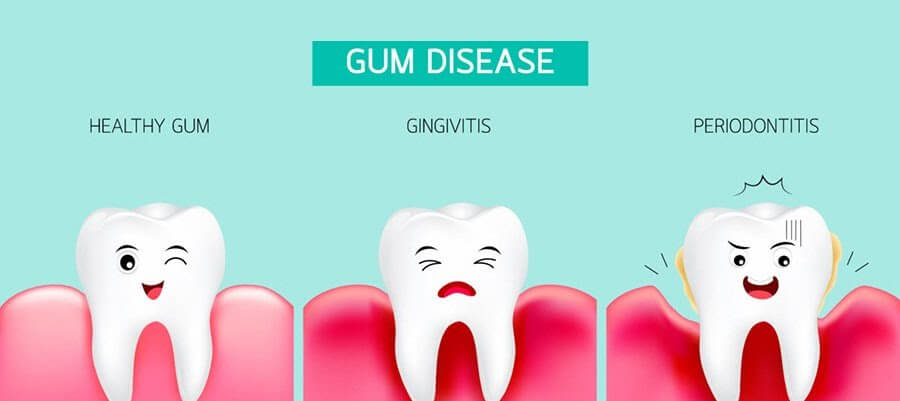

- Preventing Gum Disease: Plaque and tartar buildup can lead to gum disease, which is an infection of the gums that can cause inflammation, bleeding, and even tooth loss if left untreated. Dental scaling removes the plaque and tartar that can cause gum disease, helping to keep the gums healthy.

- Gum Disease: If you have gum disease, dental scaling may be necessary to remove plaque and tartar buildup that has accumulated below the gumline. This can help to reduce inflammation and bleeding of the gums and prevent further progression of the disease.